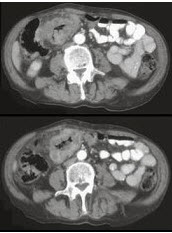

男,45岁,右下腹胀痛、并可触及质硬包块,请结合图像选择最可能诊断( )

A:结肠Crohn氏病

B:结肠癌

C:肠结核

D:结肠淋巴瘤

E:慢性溃疡性结肠炎